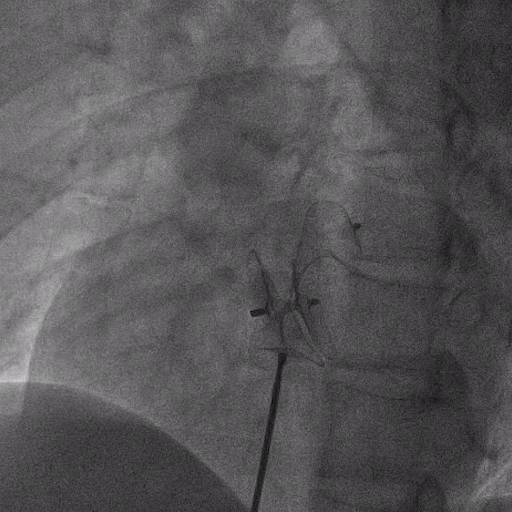

在獲得患者同意后,1月12日,尚福軍主任為患者進行了PFO封堵術。術中造影可見封堵器殘余漏,尚福軍主任用精湛的技藝,順利通過封堵器殘余漏裂縫,將右心導管從右房送入左房,且順利到達肺靜脈;遂行卵圓孔未閉封堵術后殘余漏再次封堵;且完美釋放PFO封堵器,可見兩封堵器呈“馬蹄蓮”狀,再次術中造影未見殘余漏。